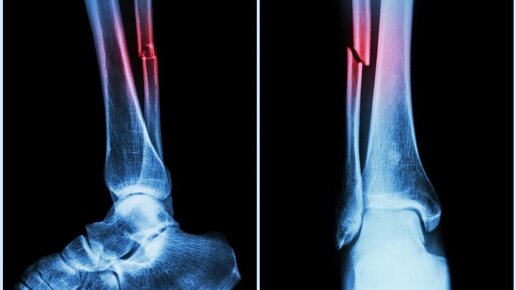

Бытует мнение, что перелом – это неудачное стечение обстоятельств. Люди не задумываются, что «перелом на ровном месте» – это не просто несчастный случай, а признак повышения хрупкости костей, вызванный остеопорозом В силу возрастных или гормональных изменений после 30 лет начинает снижаться минеральная плотность костной ткани, и к 50 годам она может достичь своего критического минимума. В результате кости становятся хрупкими, и повышается риск переломов. В чем причины хрупкости костей? Повышенная хрупкость костей (остеопороз) считается болезнью людей пожилого возраста...

Как отличить перелом от ушиба?! Моя история сломанной ноги.